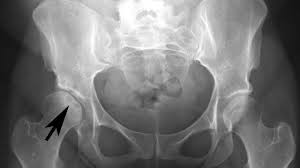

La osteonecrosis como la de Jacinto, paciente que acudió a nuestra consulta por osteonecrosis bilateral de fémur, se debió al uso crónico de corticoides por una enfermedad autoinmune.

Inicialmente el hueso y la médula ósea se degeneran manteniéndose vivo el cartílago que se alimenta de los nutrientes del líquido sinovial. Aparecen lesiones líticas con destrucción de la matriz trabecular y reemplazo en los huecos por tejido graso. La imagen radiológica no es muy llamativa, pero hay dolor y daño en los tejidos analizados al microscopio.

Posteriormente la lesión más clara se subraya con una imagen de esclerosis alrededor como si el hueso sano circundante intentara rodear la lesión, lo que además es más marcado en la gammagrafía.

En la última, hay destrucción, fractura y separación de los fragmentos óseos dañados, acompañando al cartílago sano que pierde el soporte. En suma, se hunde la superficie articular por destrucción de los pilares que constituyen la trama ósea.

La sintomatología de dolor en la ingle en reposo y a la exploración, y en los esfuerzos, giros y movimientos, es progresivamente invalidante y el diagnóstico radiológico suele confirmar las sospechas.